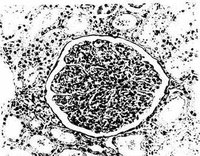

(3)腎小管上皮細胞管型(renal epithelial cast):也稱腎上皮細胞管型。因管型形成於腎小管內,所以被包容的上皮細胞就是脫落於腎小管壁的腎小管上皮細胞。其可分為兩大類:一類是由脫落的腎小管上皮細胞與T-H蛋白組成,成片上皮細胞與基底膜分離,脫落的腎小管上皮細胞粘在一起;另一類為急性腎小管壞死時,胞體較大,形成多變,典型的上皮細胞呈瓦片狀排列,充滿管型,細胞大小不等,核形模糊,有時呈淺黃色。此管型常難與白細胞管型區別,但管型內腎小管上皮細胞比白細胞略大,可呈多邊形,形態變化比白細胞複雜,含有一個較大的細胞核,可用加酸法呈現細胞核。酯酶染色呈陽性,過氧化物酶染色呈陰性,藉此可與白細胞管型鑑別。